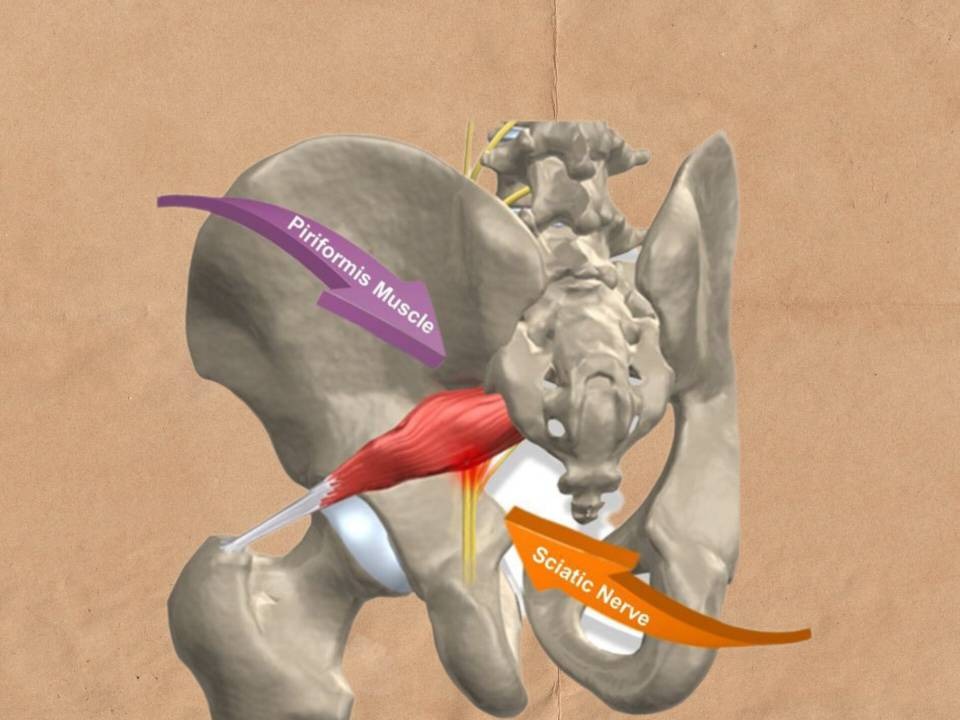

درد سیاتیک

از کمر شروع می شود و در باسن، پشت ران و ساق ادامه می یابد. معمولا به طور ناگهانی شروع می شود. در این ناحیه های گفته شده بی حسی و ضعف هم گزارش می شود.

عصب سیاتیک

بزرگ ترین عصب بدن است که از باسن و پشت پا می گذرد. این عصب در هر دو سمت، پای چپ و راست وجود دارد. هر گونه فشار بر روی این عصب منجر به درد در همه طول عصب می شود. درد سیاتیک بیشتر در سن 30 تا 50 سالگی گزارش می شود.

علت های درد سیاتیک

عوامل متفاوتی در درد سیاتیک وجود دارند که مهم ترین آن ها شامل:

1- پارگی دیسک: بیرون زدگی دیسک می تواند عصب سیاتیک را تحریک کند به طوری که منجر به درد و بی حسی شود. تا 5% کمر درد ها ناشی از بیرون زدگی دیسک اند.

2- تنگی کانال نخاعی: به جهت تنگی و باریکی بیش از اندازه کانال نخاعی فشار به نخاع وارد می شود.

3- لغزش مهره یا اسپوندیلولیستزیس: به رانده شدن یک مهره به سمت جلو بر روی مهره زیرین.

4- سندرم پیریفورمیس: اختلال در عضله پیریفورمیس به طوری که عضله سفت و منقبض می شود و عصب سیاتیک را تحریک می کند. این عضله در ناحبه باسن قرار دارد.

علائم درد سیاتیک

ضعف عضلانی، بی حسی، حس سوزش، درد، از دست دادن حرکت در پا ها، گزگز شدن یا سوزن سوزن شدن و بی اختیاری ادرار از مهم ترین علائم درد سیاتیک به شمار می آیند.

درد سیاتیک یکی از دلایل شایع کمر درد و درد در پا ها است.

تشخیص و درمان درد سیاتیک

هدف درمان درد سیاتیک کاهش درد و افزایش دامنه حرکتی است. از مهم ترین روش های درمانی این درد می توان به فیزیوتراپی اشاره کرد. در فیزیوتراپی درد سیاتیک اولویت نخست تمرین درمانی است به طوری که با ورزش های هدفمند می توان درد سیاتیک را مهار کرد. هم چنین درمان دستی از سوی فیزیوتراپیست یا مدالیته های الکتروتراپی می تواند مورد استفاده قرار گیرد. در فیزیوتراپی درد سیاتیک از سوزن خشک نیز استفاه می شود. ماساژ و کیسه گرم هم می تواند مورد استفاده قرار گیرد. جراحی درد سیاتیک تنها در موارد شدید انجام می گیرد.